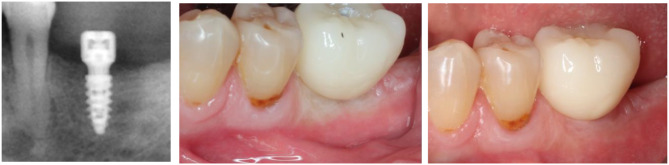

Method and results: The digital workflow involves 3 intra-oral scans (IOS), IOS#1 at completion of the soft tissue healing, IOS#2 at prosthesis delivery, IOS#3 after soft tissue conditioning, and the STL files of the healing cap, the abutment, the implant and the prosthetic crown. The above are superposed and merged following a dedicated protocol that provides access to the distance the delivered crown deforms the strained gingiva. The present case study displayed distinct blanching intensities. Severe blanching was present when the strains applied to the gingiva caused a displacement of 1.3 mm and above; a displacement of 0.9 mm led to moderate blanching. No blanching was observed up to a displacement of 0.6 mm.

Conclusion: A digital protocol, involving the superposition and merging of IOSs taken along a defined timeline and STLs of the implant hardware, allowed measuring the displacement distances a prosthetic crown wields upon delivery on the gingiva beneath the prosthesis. Various intensities of gingiva blanching could be related to distinct displacement distances of the healed gingiva that were triggered by attaching a prosthetic crown to the implant neck.